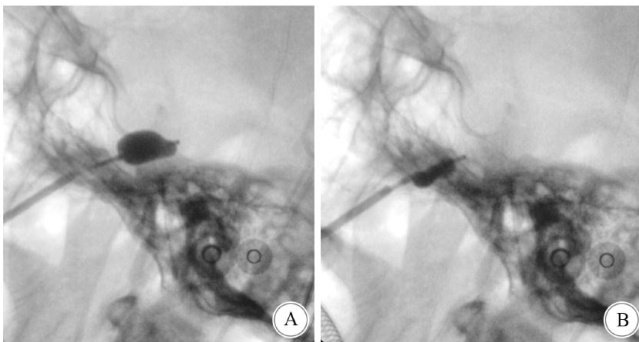

Comparative study on modified percutaneousballoon compression and microvascular decompresson i(剩余13209字)

改良经皮穿刺球囊压迫术与微血管减压术治疗单纯第Ⅲ支三叉神经痛的对比研究